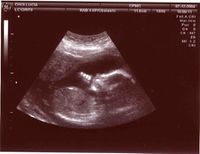

صورة موجات تصواتية لجنين داخل الرحم

صورة موجات فوق صوتية لجنين داخل الرحم في أسبوعه الرابع عشر

من الاستخدامات المهمة للموجات التصواتية هو استخدامها في الطب وبالذات في الكشف عن الجنين في بطن أمه وهل هو حي أم ميت ، حيث أنه عندما يسلط الطبيب مصدر تلك الموجات على رحم الام تنعكس تلك الموجات وعندما يكون قلب الجنين ينبض فان زمن انعكاس أو ارتداد تلك الموجات يختلف تبعا لانقباض عضلة قلب الجنين وانبساطها وذلك يعود لتغيير بسيط في المسافة التي تقطعها الموجة قبل أن ترتد ، مما يعطي الجهاز المستقبل للموجات المنعكسة الفرصة لتسجيل تلك النبضات وبالتالي تظهر على شاشة الطبيب حركة القلب أي أن الجنين يكون حيا ، لكن لو كان الجنين ميتا فإن الموجات ترتد في نفس الزمن.